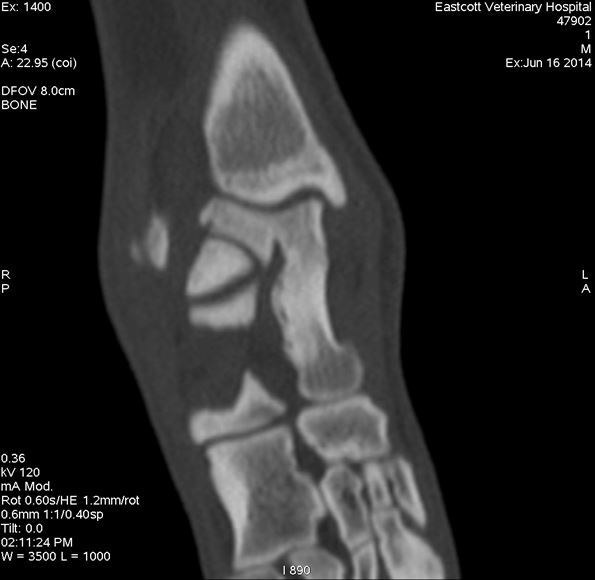

Dorsal plane image through the medial talar ridge showing fissure fracture parallel to medial cortex

Figure 2